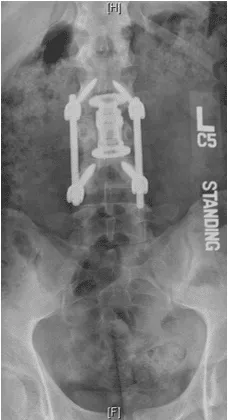

Patient was operated and the spinal canal cleaned up of all bony fragments. The spine was fixed from the side and the back to take care of instability.

Patient was sent to a rehab facility after the surgery and she made a quick and complete recovery in 5-6 months.